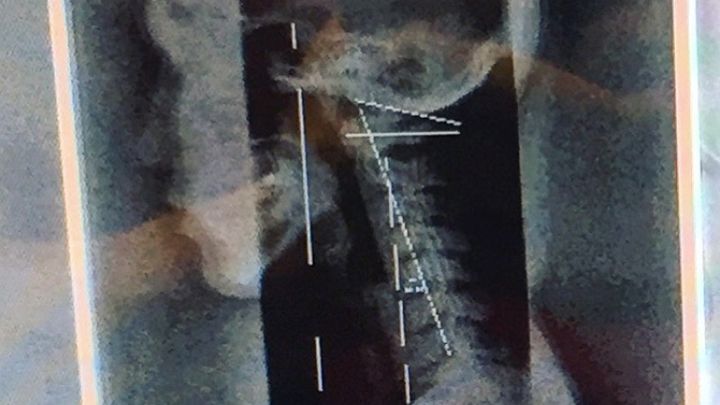

Within the past two months I have since learned, via x-ray, that my neck itself is actually sitting pretty at negative fourteen degrees. This has been putting pressure on a good amount of my nerves that usually sweep under the base of the skull and reaches like vines down the spine and out to my innards. Within two weeks of learning about my neck, I ended up fainting in the shower, smacking my head, and getting a concussion.